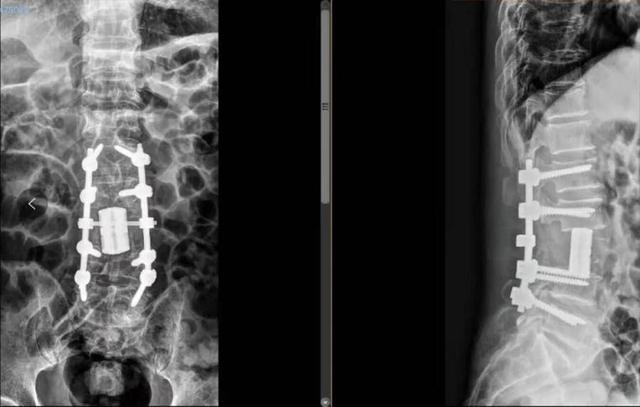

△3D打印术后人工椎体植入脊柱重建良好。